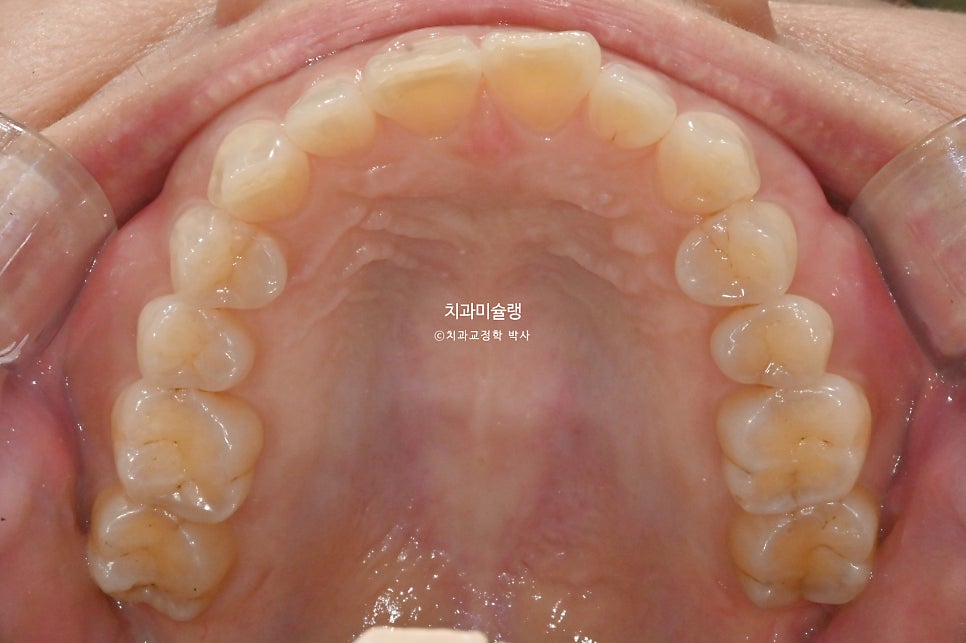

초진 시 구강 상태 분석

환자기준 우측 치아들이 내려와 있습니다. 앞니가 깊게 물리는 과개교합 입니다. 중심선 불일치도 보입니다.

어금니 교합은 좋은편.

과개교합, 인비절라인라이트로 충분하여 인비절라인라이트 권유드렸습니다. 블랙트라이앵글을 예방하기 위해 치간삭제도 소량 필요합니다.